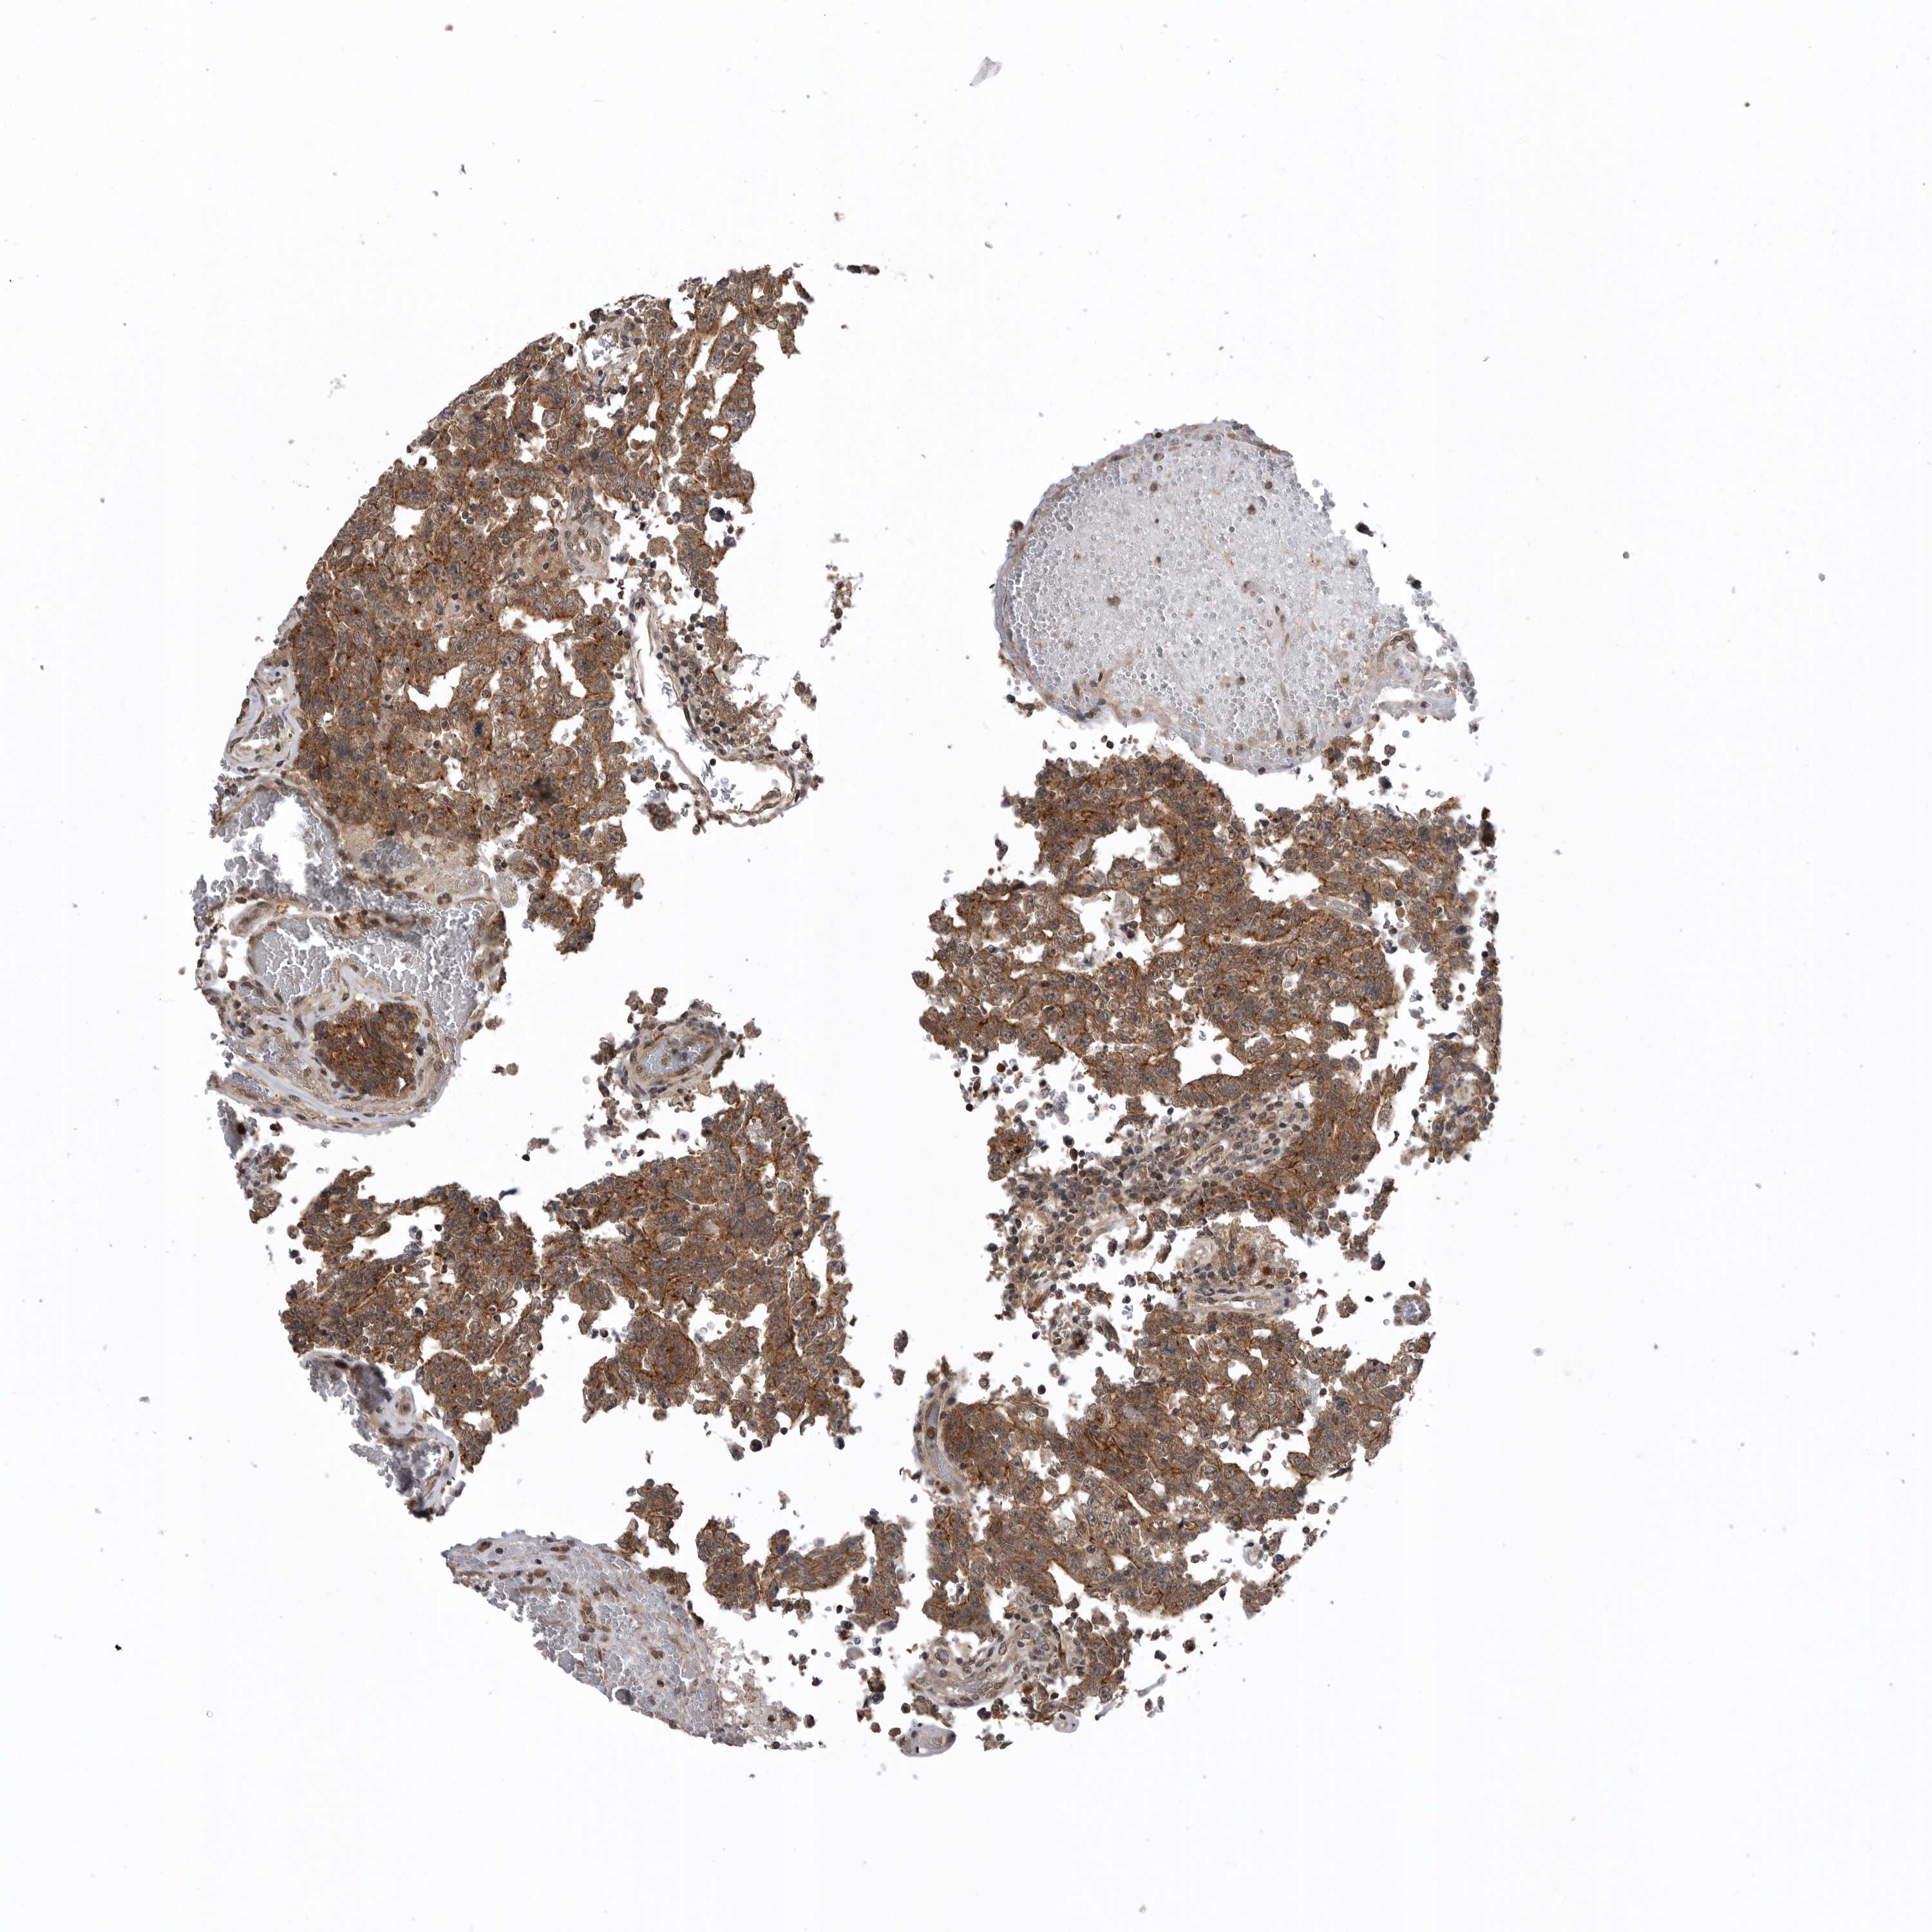

TESTIS CANCER - Protein expressioni

A mouse-over function shows sample information and annotation data. Click on an image to view it in a full screen mode. Samples can be filtered based on level of antibody staining by selecting one or several of the following categories: high, medium, low and not detected. The assay and annotation is described here.

Note that samples used for immunohistochemistry by the Human Protein Atlas do not correspond to samples in the TCGA dataset.

Antibody stainingi

Antibody staining in the annotated cell types in the current human tissue is reported as not detected, low, medium, or high, based on conventional immunohistochemistry profiling in selected tissues. This score is based on the combination of the staining intensity and fraction of stained cells.

Each image is clickable and will lead to virtual microscopy that enables deeper exploration of all samples and also displays staining intensity scores, fraction scores and subcellular localization as well as patient and tissue information for each sample.

Antibody HPA021666

Antibody HPA026716

Staining

High

Medium

Low

Not detected

Intensity

Strong

Moderate

Weak

Negative

Quantity

>75%

75%-25%

<25%

None

Location

Nuclear

Cytoplasmic/membranous

Cytoplasmic/membranous,nuclear

Carcinoma, Embryonal, NOS

Seminoma, NOS